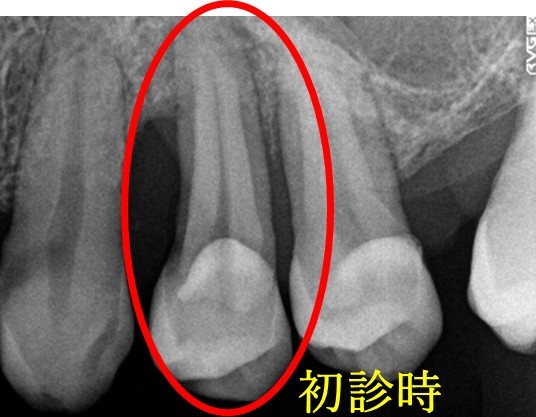

「右下の1番後ろの歯が浮いたような感じで、グラグラしていて噛むと痛みもあります。」とのこと。レントゲンで詳しく調べると、噛み合わせの問題と歯周病の進行が原因で、奥歯の周りの骨がなくなってしまっていました。この歯は残念ながら抜歯になることをYさんにお話しし、他の歯が多く残っているので、インプラント治療をおすすめしました。(インプラントは他の歯に負担をかけないので、残っている歯を守ることができます。)

この時はYさんはしばらく様子を見ることにされましたが、5月に再び来院され、「インプラントをお願いします」と決心してくださいました。合計2本のインプラントを入れ、Yさんは、「左右の歯で食べ物が噛めるようになり本当に良かったです。今後も歯を大切にしたいと思います。」と、とても嬉しそうにされていました。